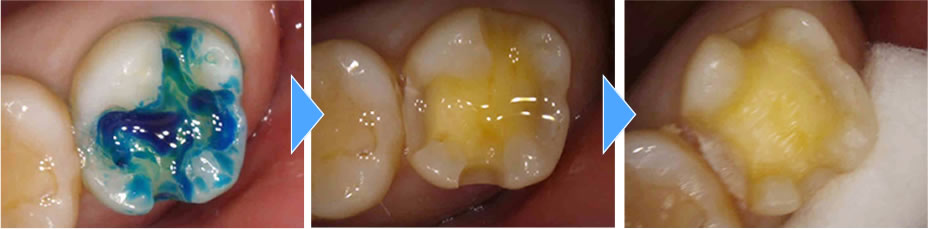

虫歯治療の実施

むし歯検知液を使用し、むし歯がしっかりと取り切れたかどうか確認後、神経の保護をしてから型取りをしました。

セラミックインレーの装着・治療完了

完成したセラミックインレーを装着し、咬み合わせを調整して治療完了です。